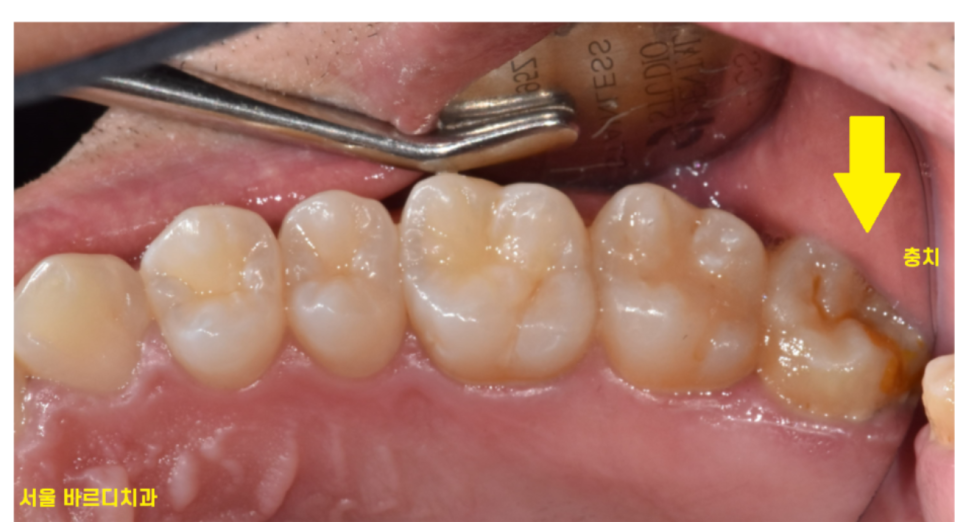

230725 맨 끝 어금니가 잘 안닦이다보니 충치가 생겼어요~

잘 닦이지 않다보니 충치도 쉽게 생기고

음식물 찌꺼기가 그대로 남기 쉬운 구역이라 그렇습니다 .

아무리 꼼꼼히 양치한다고 해도 관리 사각지대가 되기 쉽거든요~